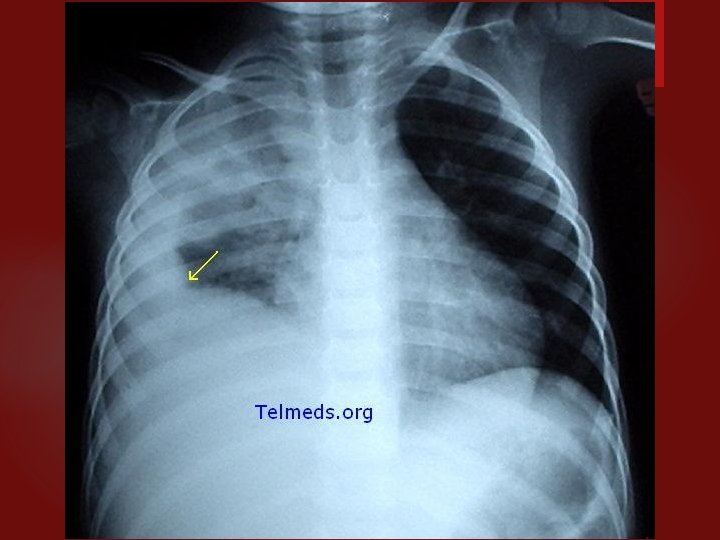

Junio 27 del 2006 Proceso fibrótico no neumónico

NEUMONIA AGUDA Caracteristicas clínico-radiológicas Etiología bacteriana: consolidación lobar, cavitación y derrame pleural. Compromiso difuso bilateral: etiología viral, neumonía atípica y por pneumocystis carinii. Staphylococus aureus: de focos múltiples, neumatoceles. Legionella: de focos múltiples, progresión radiológica rápida. Necrotizante, con abscesos o empiema: por gramnegativos, estafilococo, por anaerobios.